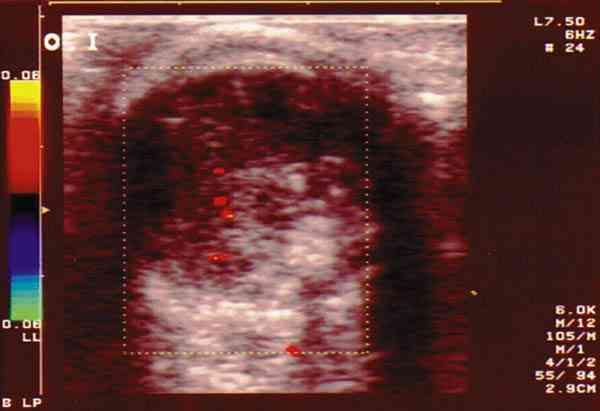

|

Figura 4. Retinoblastoma de localización anterior, vascularizado.

Figura 5. Retinoblastoma que ocupa la totalidad del vítreo

parcialmente calcificado y con escasa vascularización.